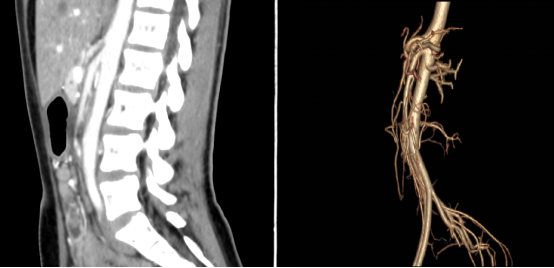

为此,儿科团队又完善了肠系膜动脉造影及三维成像,检查结果提示:肠系膜动脉与腹主动脉小于20度,左肾静脉及十二指肠明显受压。至此,小弦被确诊为肠系膜上动脉压迫综合征。